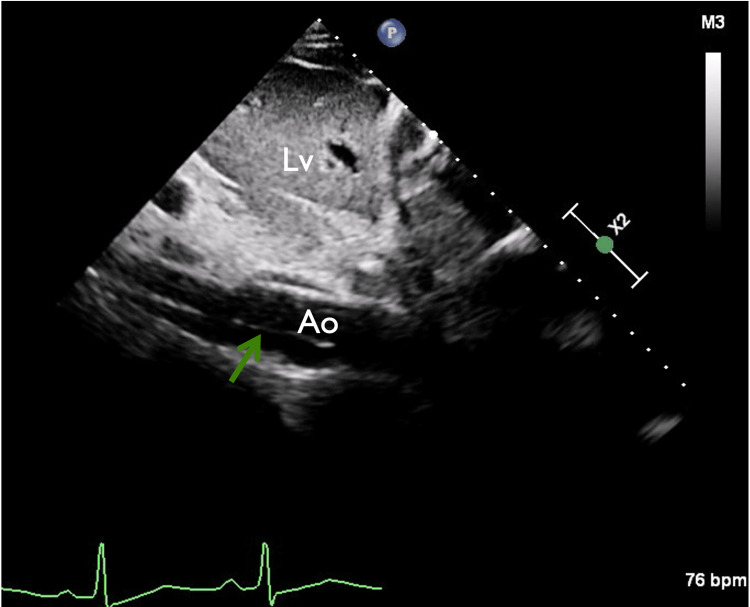

In view of chest pain associated with positive cardiac biomarkers, he was admitted to the Coronary Care Unit on intravenous nitroglycerin. While waiting for his admission, he suddenly had recurrent chest pain associated with marked hypotension (75/43 mmHg), for which the intravenous nitroglycerin was discontinued, fluid resuscitation was provided, and he was temporarily started on intravenous norepinephrine. The on-call cardiology team was contacted for an emergent evaluation. Subsequent ECG showed nonspecific ST-segment changes in leads V5-V6 (Figure 1). An emergent bedside echocardiogram revealed a moderate pericardial effusion of hemodynamic significance (Figure 2), as suggested by partial right ventricular chamber collapse (Figure 3) early in diastole and a plethoric non-collapsing inferior vena cava. The pericardial effusion also contained echogenic strands, which are highly concerning for blood clots. Additionally, a moderate to severe aortic valve insufficiency (Figure 4) was present according to color Doppler findings and pressure half-time assessment (315 ms). An intimal flap was visualized on the ascending and descending aorta, suggesting an extensive AD (Figures 2–6). A computer tomographic angiogram (CTA) of the chest and abdomen revealed a large pericardial effusion with an extensive AD extending from the level of the ascending aorta into his right brachiocephalic artery, the right and left common carotid arteries, and inferiorly to the right iliac artery (Figures 7–10), although not occlusive in diameter (or clinically). These findings were consistent with an extensive Stanford type-A AD with rupture into the pericardium, for which volume expansion and vasopressors were provided and emergently operated on the same day. The surgery included an open pericardiotomy with pericardial blood drainage, replacement of the ascending aorta from just above the commissure to the take-off of the innominate artery, partial replacement of the aortic arch, and aortic valve repair with successful results. Multiple intraoperative packed red blood cell units (8), fresh frozen plasma units (4), cryoprecipitate units (10), and platelet apheresis (3) were provided in view of bleeding complications related to the arrival provision of dual antiplatelet and anticoagulation therapy prior to the diagnosis of AD.